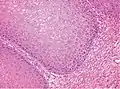

Surgeons must provide adequate specimens including the full thickness of the tumors and adjacent uninvolved mucosa for correct histopathology diagnosis.[9]

Epithelioma cuniculatum (also known as Carcinoma cuniculatum,[11]:654 and Ackerman tumor[12]) is a subtype of verrucous carcinoma,[13] characterized by well-differentiated epithelial cells which lack cytological atypia, but display a blunt papillary/pebbly surface and keratin-filled crypts extending deep into the connective tissue.[14] These keratin-filled crypts resemble rabbit burrows.[14] It is located almost exclusively on the foot,[13] but at least 50 oral locations have also been observed.[14]